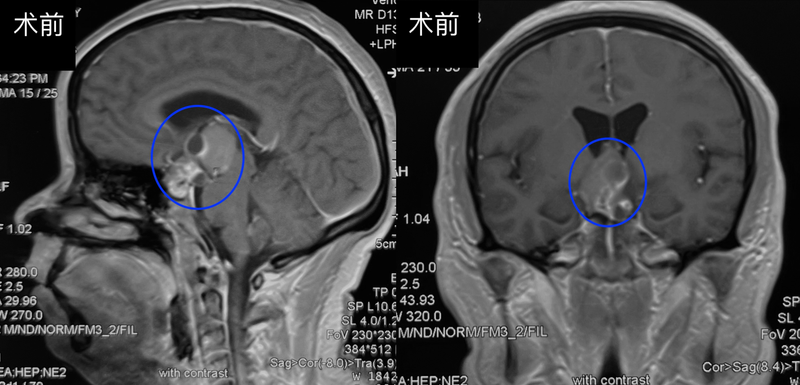

?患者女性,40歲。頭痛反復發(fā)作8年,檢查發(fā)現(xiàn)鞍區(qū)鞍上占位入院。????術前一般情況可,視力視野檢查正常。術前MR提示:鞍區(qū)鞍上第三腦室內(nèi)外囊實性占位。腫瘤已完全占據(jù)第三腦室前部,上方達兩側(cè)室間孔。側(cè)方擠壓腦室壁,和下丘腦區(qū)域關系密切,后方擠壓中腦。考慮顱咽管瘤。CT提示腫瘤部分鈣化。????采取內(nèi)鏡經(jīng)鼻入路顱咽管瘤切除術。術中見腫瘤起源于垂體柄近端、下丘腦區(qū)域。術前影像所見的鈣化部分,大大提升了手術難度,好在沒有重要血管及穿支在鈣化灶內(nèi)穿行,仍能全切腫瘤。????術后患者恢復良好,術后3天復查核磁提示腫瘤全切。術后病理:成釉質(zhì)細胞型顱咽管瘤。(江蘇省人民醫(yī)院神經(jīng)外科陶超)